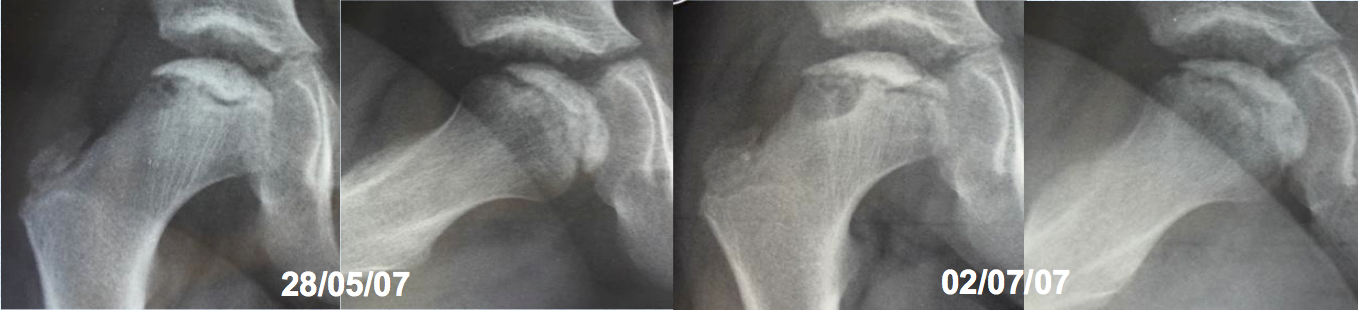

Enfermedad de Legg-Perthes-Calvé recurrente. Descripción de un caso y revisión de la literatura. [Recurrent Legg-Perthes-Calvé disease. A case report and literature review]